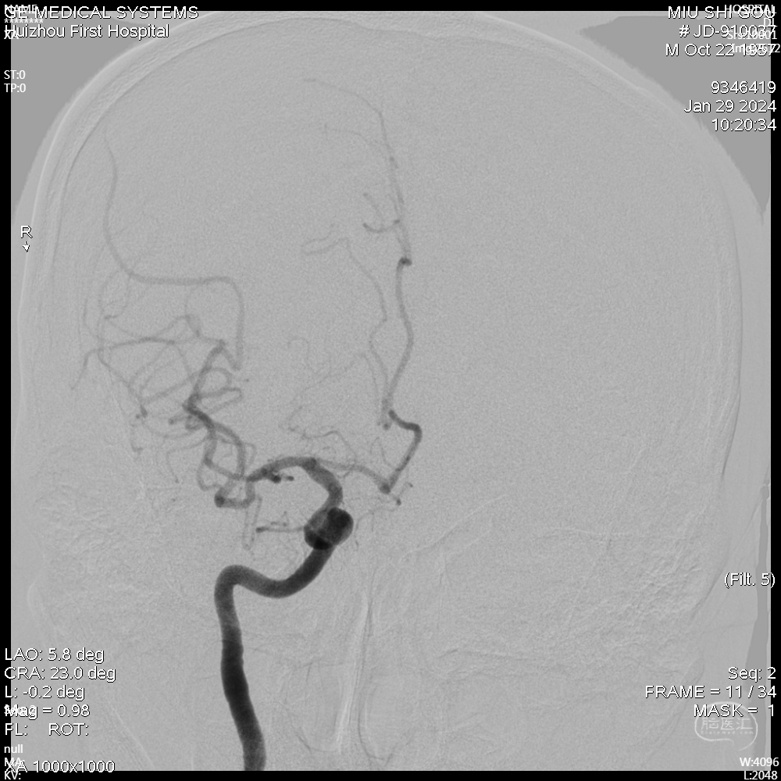

急诊DSA未见畸形血管。

术前诊断:1.脑出血2.高血压3.右侧大脑中动脉中度狭窄。

急诊DSA(右侧颈内正位)